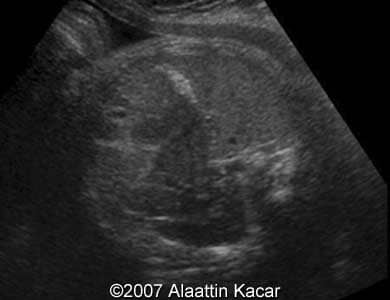

These are some images of a fetus with hyperechoic content of the gallbladder. We assumed presence of gallstones in the fetus.

Images 1, 2: Transverse scans through the abdomen at the level of the gallbladder showing its hyperechoic content.